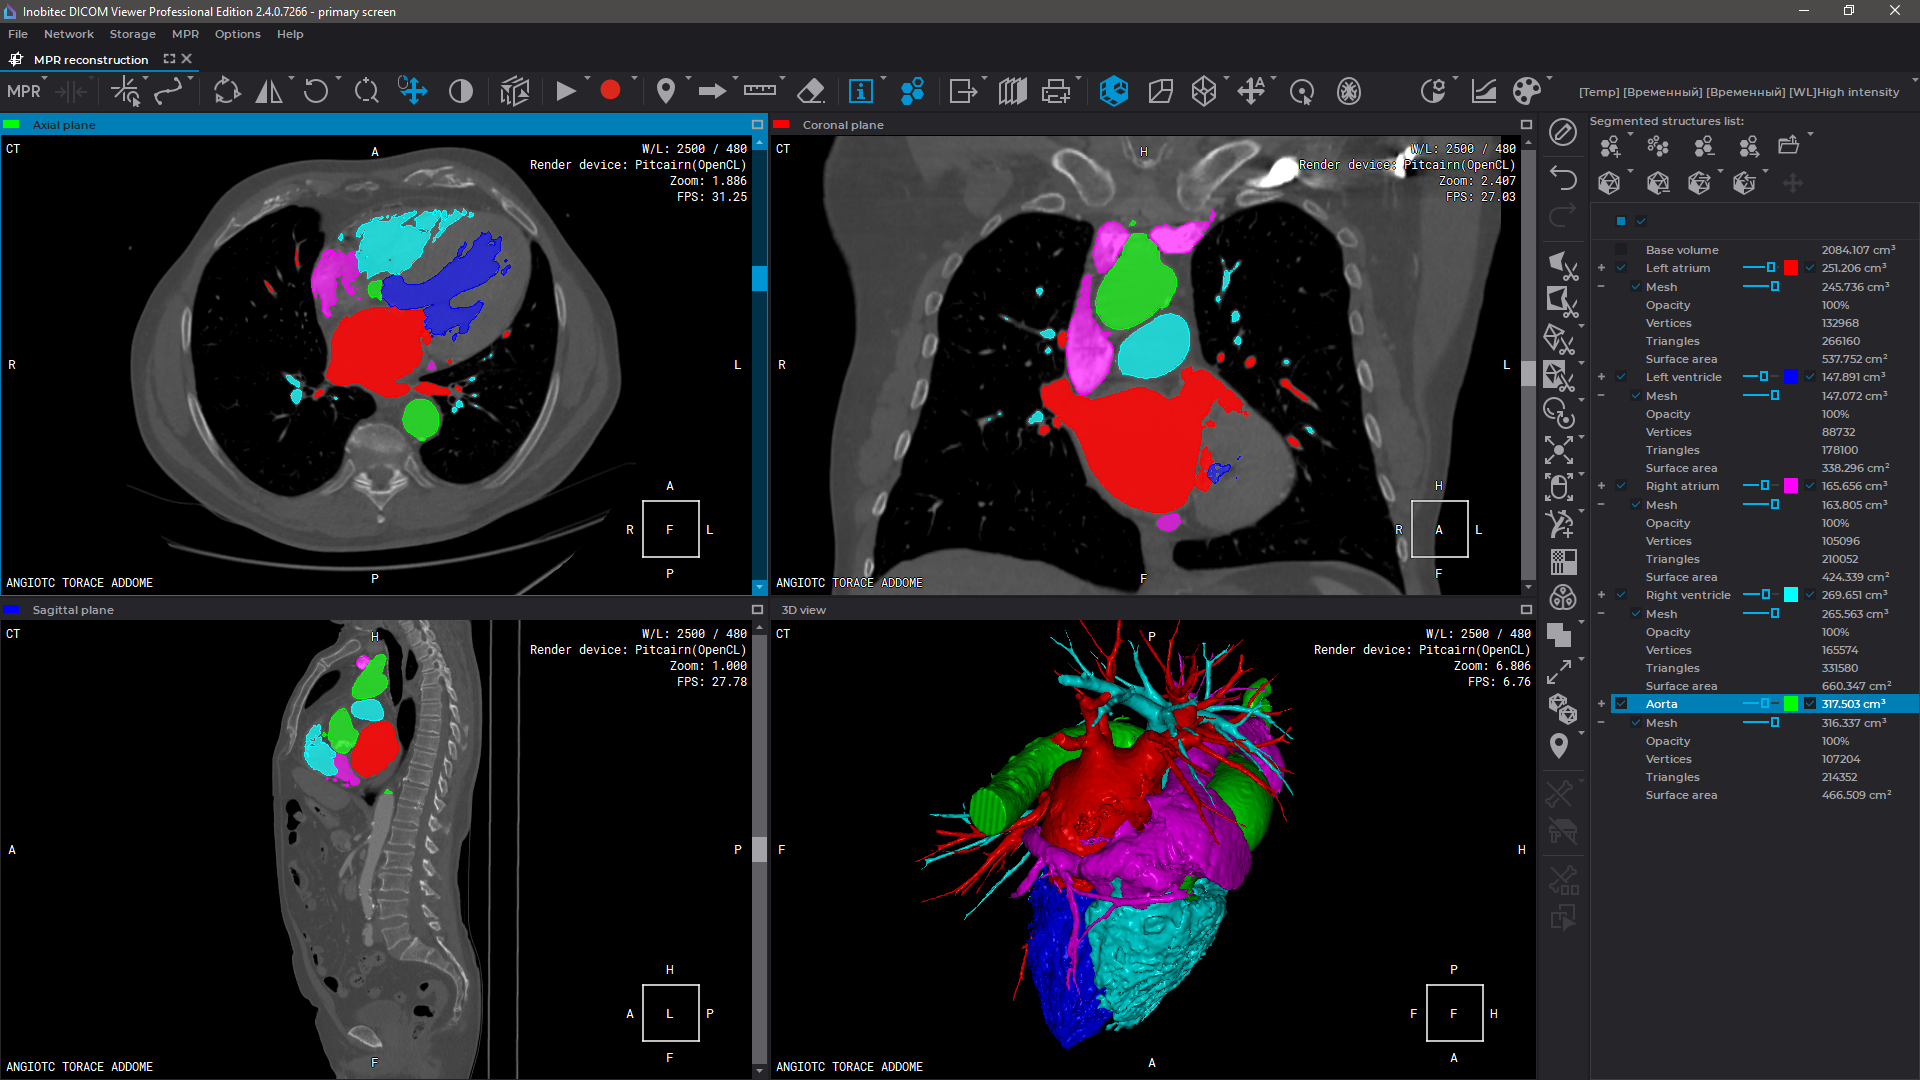

Advanced capabilities for working with 3D reconstructions

Export surfaces in OBJ, STL, PLY, and GLB formats